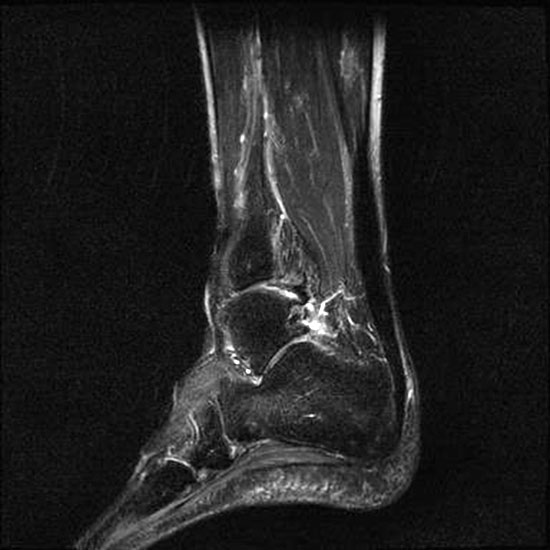

Hier befindet sich ca. 3-5 cm proximal des Tuber calcanei ein als „kritische Zone“ benannter Bezirk, der durch eine ungünstige arterielle Blutzufuhr gekennzeichnet ist (letzte Wiese). Hier finden sich häufig spindelförmige Schwellungen, die bei MRT-Diagnostik nicht selten partielle Nekrosen und Partialrupturen der Achillessehne aufweisen (Abb. 14).

Die sonographische Diagnostik eignet sich primär zur Erkennung schmerzhafter Prozesse im Verlauf der Achillessehne und kann bei Bedarf durch Röntgen bzw. MRT ergänzt werden. Besonders bei längeren Verläufen und kräftigen spindelförmigen Schwellungen (>9mm, Normwert <5mm) im Bereich der kritischen Zone sollte ein MRT zum Ausschluss von Nekrosezonen und Partialrupturen vor Therapiebeginn veranlasst werden. Die sonographisch leicht zu erfassende Veränderung der Sehnendicke im mittleren Sehnenanteil ist ein guter Indikator für die Schwere der Erkrankung und die Beurteilung des Behandlungsverlaufes. Die sichtbaren Veränderungen am distalen knöchernen Ansatz der Sehne sind diskreter.

Insbesondere bei größeren Partialrupturen (Abb. 14) sollten operative Verfahren erörtert werden. Kleinere Partialrupturen sind der ESWT gut zugänglich, wie die beiden nachfolgenden Beispiele zeigen:

In Abhängigkeit des Befundes kann die Verwendung eines Vacoped-Stiefels für die Zeit der Therapie sinnvoll sein. Eine MRT-Kontrolle nach Therapie einer Partialruptur kann nach 5-6 Monaten durchgeführt werden.